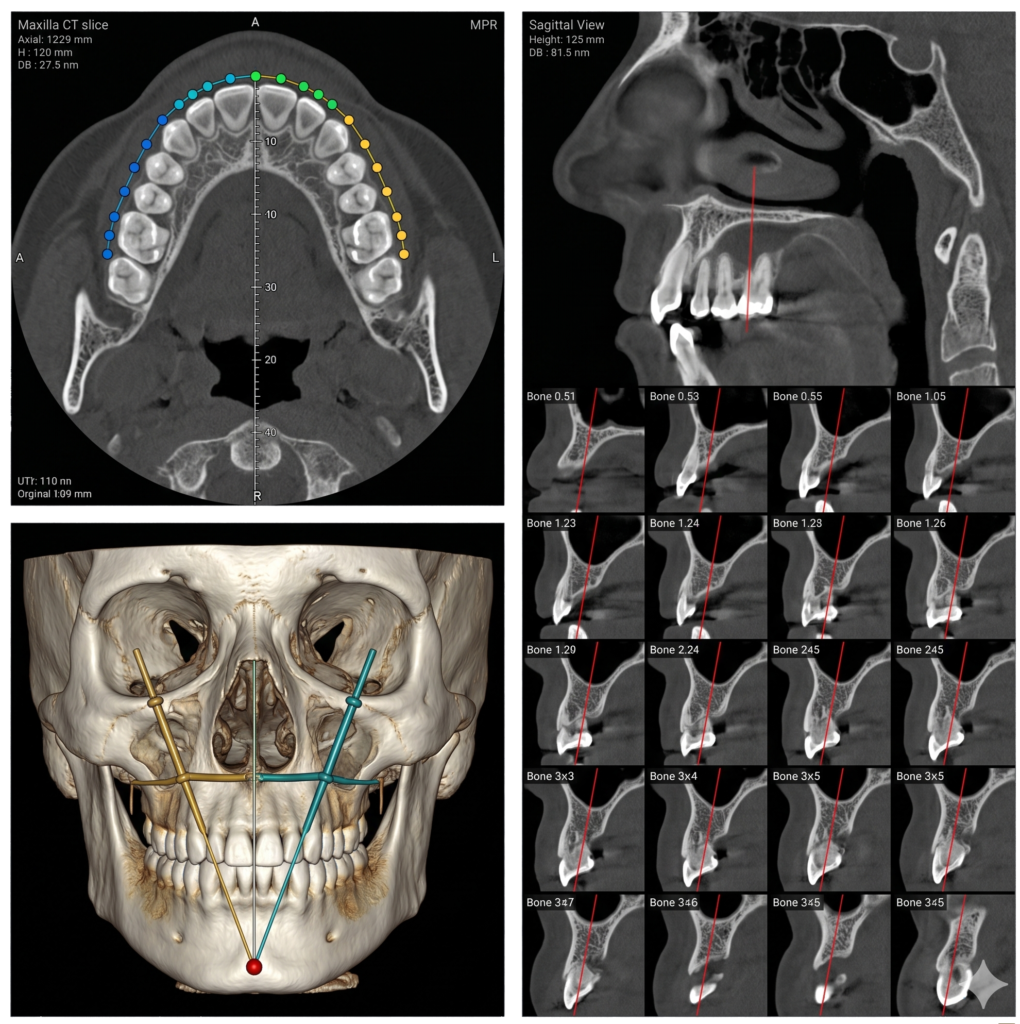

Advanced CBCT & Dental Imaging Services provide precise, high-resolution 3D scans for accurate diagnosis and treatment planning. Using modern technology, we ensure fast, reliable results with minimal radiation exposure. Our expert team focuses on patient comfort, delivering safe, efficient imaging solutions to support dentists in achieving better clinical outcomes.

He is certified in Cone Beam Computed Tomography (CBCT) and has extensive experience in advanced radiological diagnosis. Dr. Singh is associated with several reputed centers across India as a consultant radiologist for CBCT reporting. His expertise includes implant planning, impacted teeth localization, oral and maxillofacial pathology interpretation, TMJ assessment, maxillary sinus evaluation, and airway analysis.